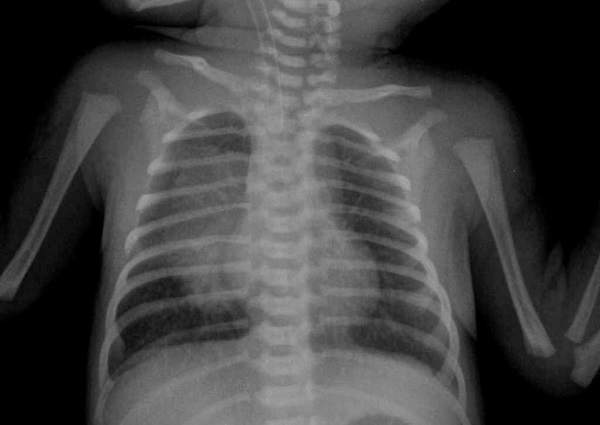

Начальная диагностика дыхательных органов осуществляется через физикальное обследование грудной клетки. Врач также проводит осмотр горла и носа. Тембр кашля и наличие или отсутствие определенных звуков при дыхании могут указать на причину его появления. Например, свистящие звуки могут свидетельствовать о том, что кашель вызван астмой.

Наиболее распространенным методом диагностики кашля является рентгенография, которая отличается высокой степенью надежности.

Лабораторные исследования применяются в тех случаях, когда после рентгенографии возникают подозрения на инфекцию. В рамках лабораторного анализа проводится исследование крови. Если есть подозрение на коклюш, дополнительно анализируется содержимое носоглотки и быстрые антигены.